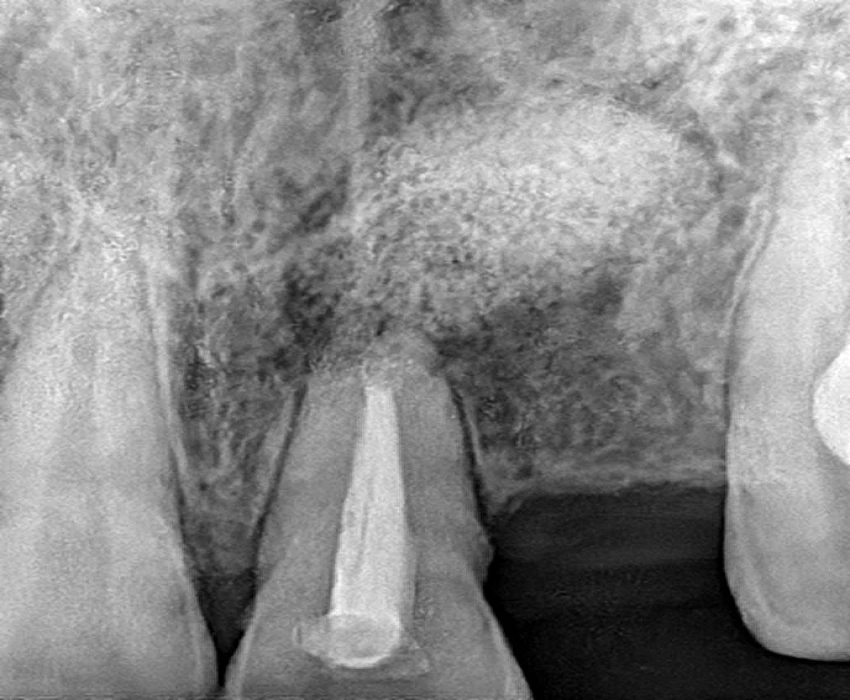

Investigation- CBCT, Viral markers, CBC, BT, CT

DIAGNOSIS- irreversible pulpitis with periapical granuloma.

TREATMENT- Faulty prosthesis is removed in respect to 22, with the help of tapered fissure. Access Opening is done' in respect to 21, under La. Working length is determined . Canals are prepared using Hyflex CM and obturated using Gutta percha using lateral condensation. Microperiosteal flap is raised. Window preparation irt 21 , periapical curretage apicoectomy is done irt 21 followed by retrograde filling with bioceramic. Cavity is filled with bone graft. Sutures placed.